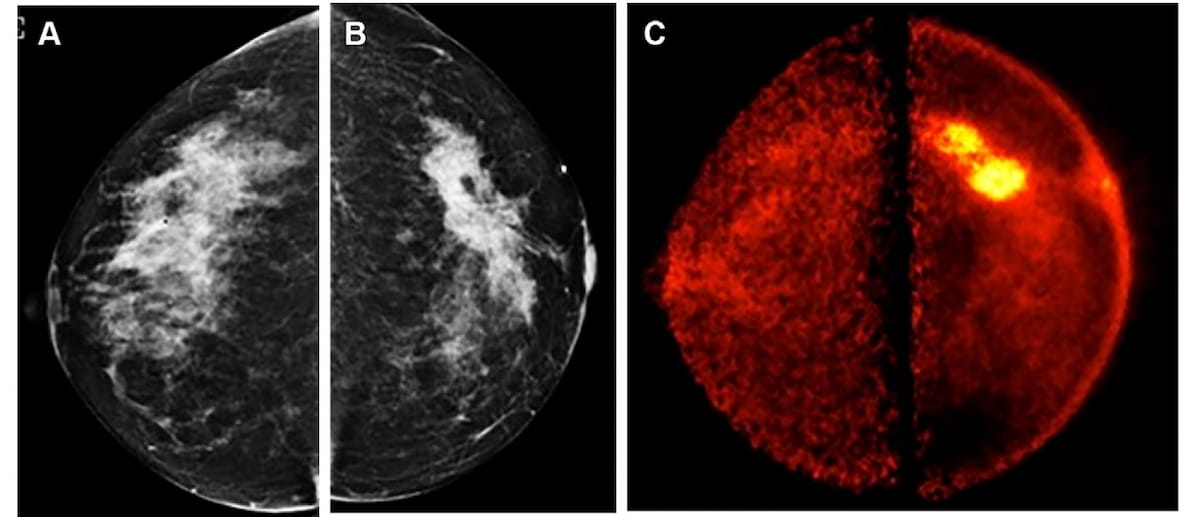

Sixty-five percent of patients with newly diagnosed high-risk prostate cancer may have extraprostatic extension on MRI, and PSMA PET/CT findings suggest those with Gleason scores of eight or higher have more than double the risk of metastasis, according to a new study presented at the European Congress of Radiology (ECR).